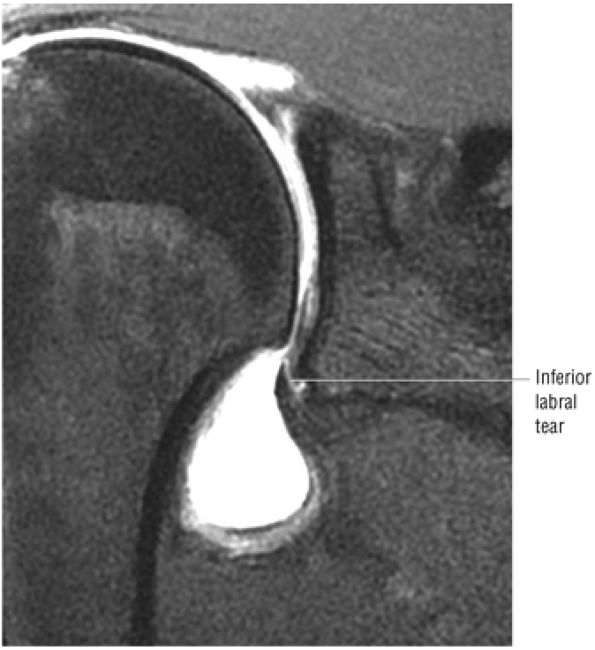

FIGURE 8.153 ● Coronal images depicting a nonacute supraspinatus tendon tear. The tears shows residual hyperintensity at the tear site on FS PD FSE images (A) and intermediate signal intensity on T2 FSE images (B).

|

![]() |